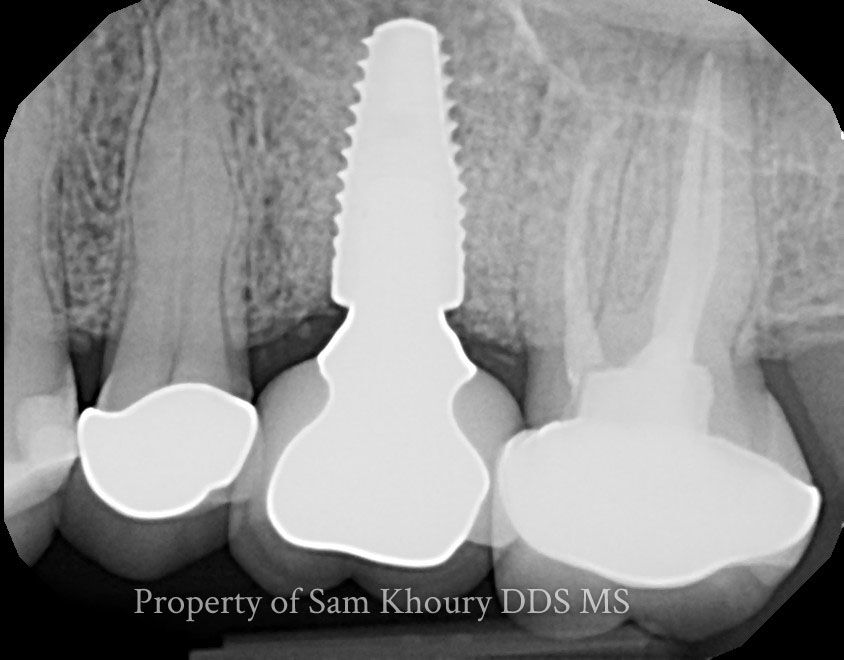

Single Dental Implant and Crown

Multiple Dental Implants

Dental Implant Bridges